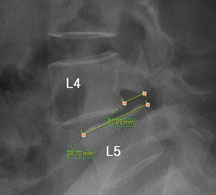

모커리한방병원 위 뼈가 50%정도 밀려나간 모습 이미지

척추전방전위증은 척추 주변, 특히 척추 후방에 있는 후관절 주변의 근육과 인대 그리고 후관절 자체가 퇴행되어 척추 뼈를 제대로 붙잡아 주지 못해 위아래 척추 뼈가 앞뒤로 밀려 나가면서 발생하는 척추질환을 말합니다.